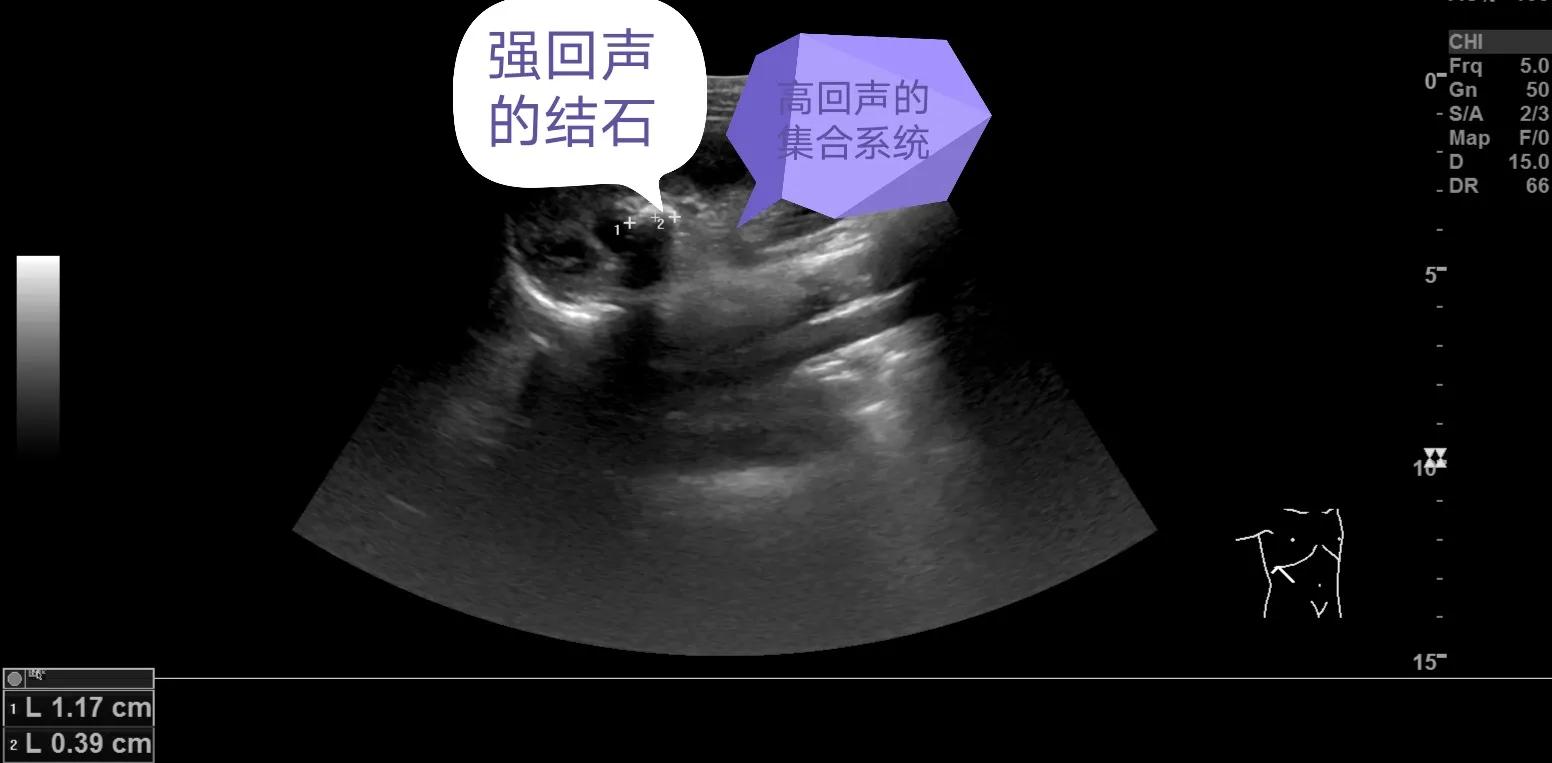

通过上述两幅图我们可以看到区别了吧,主要就是大小的区别,回声上类似,都是强回声。肾结石和肾结晶说完了,再说一下肾钙化灶,先看图片,再看区别。

肾钙化灶同样表现为肾内的强回声斑,看到这大家可能疑惑了,“大夫,刚刚区分了肾结石和肾结晶,这个明白了,一个大一个小,这会肾钙化灶也是强回声斑,这个怎么区别,这不又混在一起了”,大家别着急,图像上他们确实类似,但是发生的位置上他们是有严格的区别的,我们上面说了结晶是尿中析出的结晶,尿液在肾脏形成后通过肾乳头开口流入肾小盏—肾大盏—肾盂—输尿管—膀胱—尿道—排出体外,而肾小盏、肾大盏、肾盂和输尿管结构再加上内部的血管、脂肪结构统一构成了肾脏集合系统,又称为肾窦,这个结构在咱们超声上表现为高回声,而周围的低回声为肾实质结构,这个肾脏的回声之前的内容咱们讲过,大家可以找出来看一看,说了这个知识大家就明白了吧,肾结石和结晶一定是发生在肾脏的集合系统内,而肾钙化灶则发生在肾实质内,这是他们的本质区别,下面再给大家分享几张图,直观的感受一下。